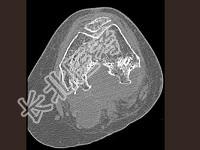

- 单项选择题男,36岁, 膝关节疼痛8年余,活动受限, 其周围可触及肿块,结合图像, 最可能的诊断是 ( )

A、骨巨细胞瘤

B、滑膜肉瘤

C、血友病性关节炎

D、色素沉着绒毛结节性滑膜炎

E、类风湿关节炎